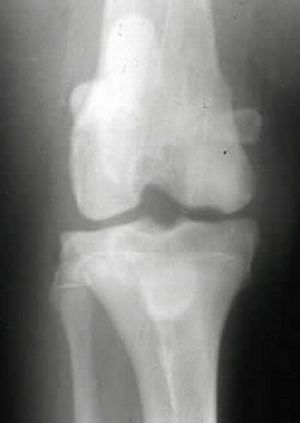

X線写真により、肘突起と尺骨との間の化骨不全による離開・転位が認められますが、その程度はまちまちです。

関節唇形成、上腕骨遠位端の変形、橈骨・尺骨近位端の骨粗鬆化、関節腔形状の不整などがみられます。

正確な診断には最大屈曲位でのX線側方向像による癒合障害部位の確認が必要です。